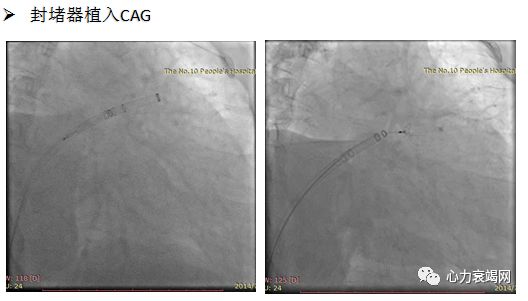

4.封堵器释放、固定、牵拉

造影提示:LAA开口最大23.4mm

选择28mm*34mm的LAmbre封堵器

术后即刻微量残余分流,直径1mm,提示成功

手术1次释放即成功,总用时90min